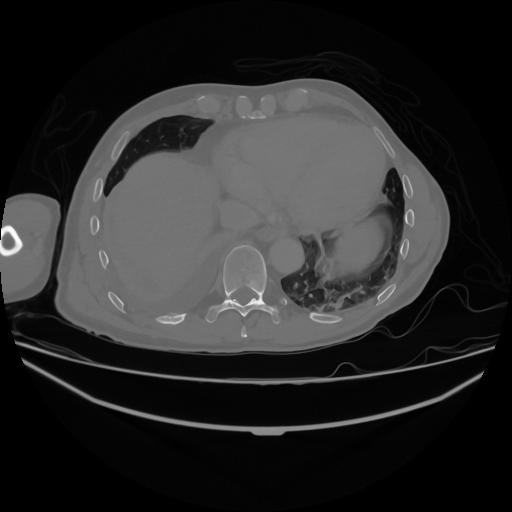

5 CUERPO,CE,Vol,1.0,CUERPO,,